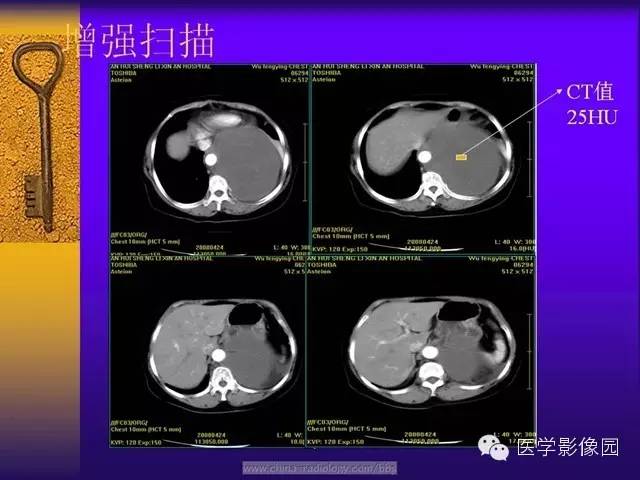

增强扫描,动脉期肿瘤的周边强化明显并见多支供血动脉显影的“地图样”强化,静脉期瘤体呈现明显不均匀强化,这与肿瘤内的细胞密集区富有薄壁的“鹿角状”分支血管密切相关。肿瘤的血管丰富区、细胞密集区强化明显,强化早期肿瘤的供血血管从肿瘤的边缘向肿瘤内部沿伸,因此,强化早期瘤内迂曲血管影显示清晰;细胞稀疏区、胶原纤维密集区、黏液变性强化相对较弱,呈现静脉期强化,坏死囊变区始终未见强化。由于SFT的病理学表现多样,因此其增强后可出现多种强化形式,动脉期肿瘤内可见迂曲的供血血管由肿瘤边缘向肿瘤内部延伸,静脉期进行性强化对于诊断及鉴别诊断具有重要意义。